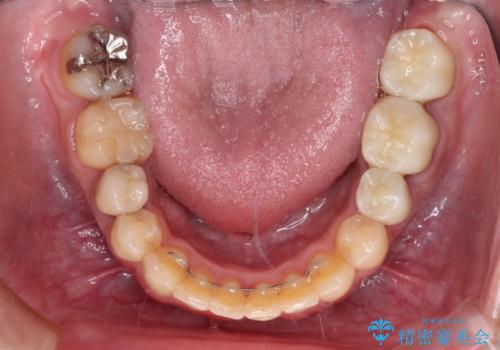

まだ銀歯が残っていますが、大きく目立つ銀歯をセラミックに置き換えることができ、人前で口を開けることを気にしなくなりました。

補綴治療中の後戻り対策をしっかりと行ったことで、歯列全体をきれいに整えることができました。